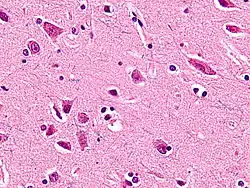

Веретенообразные нейроны или нейроны фон Экономо (названы в честь их первооткрывателя Константина фон Экономо[1]), описанные в 1929 году, являются особым классом нейронов. Для них характерно большое веретенообразной формы тело, постепенно сужающееся в единичный апикальный аксон на одном конце и единственный дендрит на противоположном конце. Кроме того, что у других типов нейронов чаще встречается большое количество дендритов, полярная форма веретенообразных нейронов уникальна. Они найдены только в двух очень ограниченных районах головного мозга гоминид: в передней поясной коре (ППК) и во фронтоинсулярной коре. Недавно эти нейроны были найдены и в дорсолатеральной префронтальной коре мозга человека[2]. Веретенообразные клетки также есть в мозге горбатых китов, финвалов, косаток, кашалотов[3][4] , афалин, серых дельфинов, белух,[5], африканских и индийских слонов.[6]

Веретенообразные нейроны — очень большие клетки относительно других клеток мозга, и они позволяют осуществлять быстрый процесс передачи информации по сравнительно крупному мозгу человекообразных, хоботных и китообразных. Некоторые ученые считают, что они играют важную роль в различных возможностях и нарушениях, связанных с приобретением знаний, в основном уникальных для людей — от восприимчивости к синдрому саванта и идеального слуха до дислексии, аутизма и психопатии.

Больше всего веретенообразных нейронов передней поясной коры найдено в организме человека, меньше у некрупных человекообразных обезьян и еще меньше у крупных. У людей и бонобо они часто обнаруживаются в скоплениях по 3-6 штук. Анализ V слоя ППК гоминид показал, что среднее количество этих нейронов у орангутанов в ППК — примерно 9 на срез; они редкие, составляют 0,6 % от всех клеток среза. У горилл их примерно 22, то есть они встречаются чаще, составляют 2,3 %; у шимпанзе их примерно 37, они обильны, составляют 3,8 %; у карликовых шимпанзе — примерно 68, они обильны и собраны в скопления, составляют 4,8 %; у людей — примерно 89, они также обильны и собраны в скопления, составляют 5,6 %.[10]